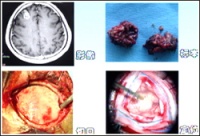

分离血管瘤

6.分离血管瘤 在紧贴血管瘤的周围,电凝及切开皮层3-4mm深(已上银夹的动脉应予切断)。用脑压板(深部要用带灯脑压板或冷光源)及吸引器在直视下小心地分离边吸引,但绝不能盲目乱掏,以免引起汹涌出血。遇到较大血管,常用动脉瘤针带线作双重结扎后切断。也可双侧上银夹后在中间电凝并切断,但银夹必须比血管的直径长,如无大型银夹,可用脑动脉瘤夹。再逐步把畸形灶分离翻转,找到深部主要供血血管,牢固结扎后切断,即可摘除脑动静脉畸形灶。

脑血管畸形--病灶